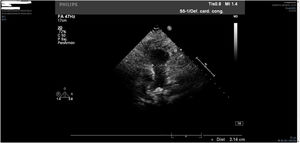

Sin embargo, en la revisión posterior a los siete años de la primera intervención, se objetivó un incremento significativo del gradiente registrado en TSVD (89 mmHg) atribuible a un componente mixto muscular subvalvular y valvular con un anillo pulmonar de 12,5 mm (z-score = -3,4) (figs. 1 y 2). El estudio preoperatorio se completó con una cardio-resonancia magnética nuclear (RMN), que además de confirmar los hallazgos ecocardiográficos nos ayudó a clarificar que el componente muscular subvalvular detectado ecocardiográficamente correspondía a un rodete fibromuscular prácticamente pegado al plano anular inferior de la válvula pulmonar (figs. 3 y 4).

El último control clínico-ecocardiográfico ambulatorio disponible muestra una paciente asintomática con estenosis pulmonar valvular leve (gradiente 23 mmHg) con anillo pulmonar de 21 mm (z = + 0,02) e insuficiencia valvular leve (figs. 5 y 6).